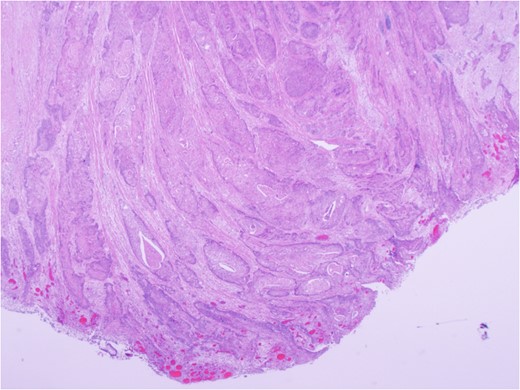

Urgent exploratory laparotomy revealed a large cecal mass invading the abdominal wall with perforation and localized abscess formation. A right hemi-colectomy was performed with irrigation and washout of the abdomen. Source control was achieved and a primary anastomosis was performed with no diversion. A Jackson-Pratt drain was left in situ. She received 3 days of IV antibiotics with transition to oral antibiotics on POD 4. Her JP drain was removed on POD 3 and she was discharged on POD 5 without complication and with a prescription for oral antibiotics. After extensive histopathology review, the cecal mass was confirmed to be an invasive squamous cell carcinoma of lung origin (Fig. 6). Specimens were sent for immunohistochemical staining. Subsequent investigations included cystoscopy and urine cytology, which were negative for urogenital carcinoma.

Carcinoma involving colonic serosa (image courtesy Dr Maisoun Abdelbaqi, Department of Pathology, Red Deer Regional Hospital, Alberta, Canada).